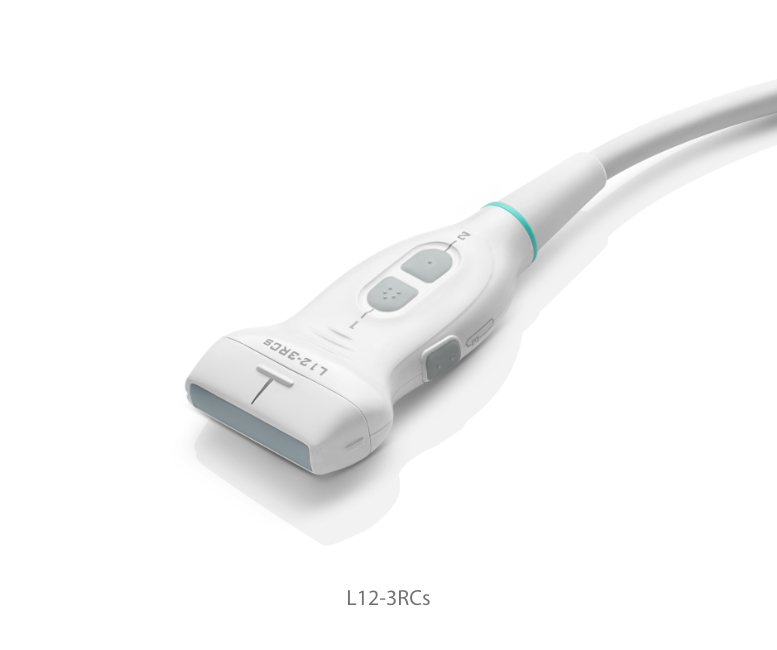

Transducers